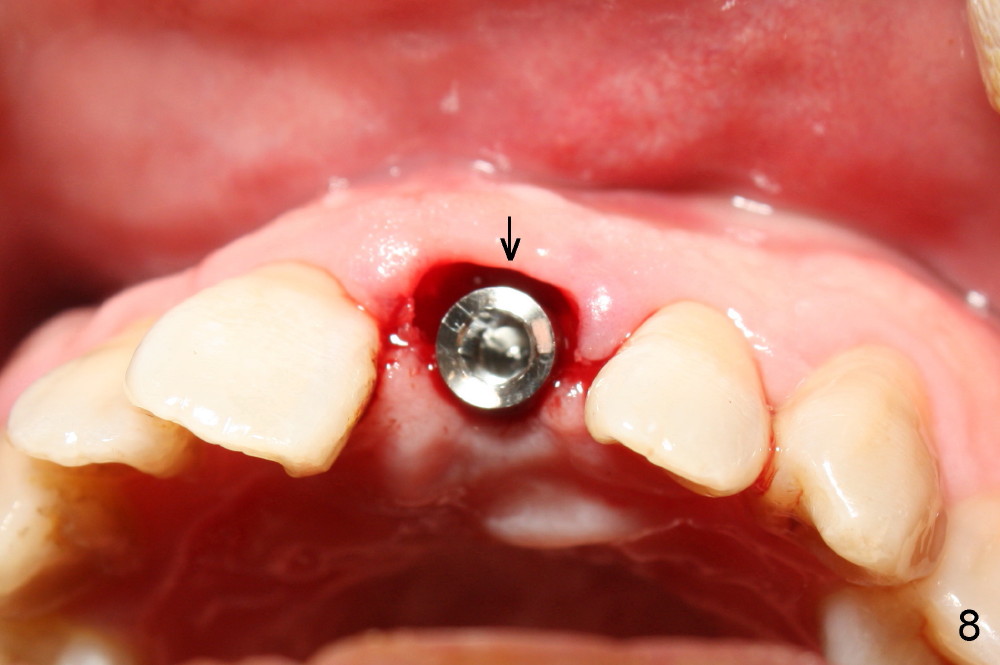

The upper right central incisor (Fig.1: #9) fractures subgingivally due to trauma for a 40-year-old man.  The incisive canal is large (I) and close to the root of the central incisor.  After extraction, the osteotomy (Fig.3b, 4: O) is made with 2 mm pilot drill (Fig.2: D) on the lingual wall (Fig.3a: L) of the socket (Fig.3a: S).  To push the incisive canal mesially, the osteotomy is enlarged by 3.5x21 mm and 4x21 mm tapered osteotomes (Fig.5,6: O).  Due to the lingual slope (Fig.7a arrow), the osteotome (blue outline) starts to deviate bucally.  To reduce this tendency, the coronal portion of the lingual slope is removed (Fig.7b: yellow circle).  The final implant (4.5x20 mm) is able to be placed as lingually as possible (Fig.7c, 8).